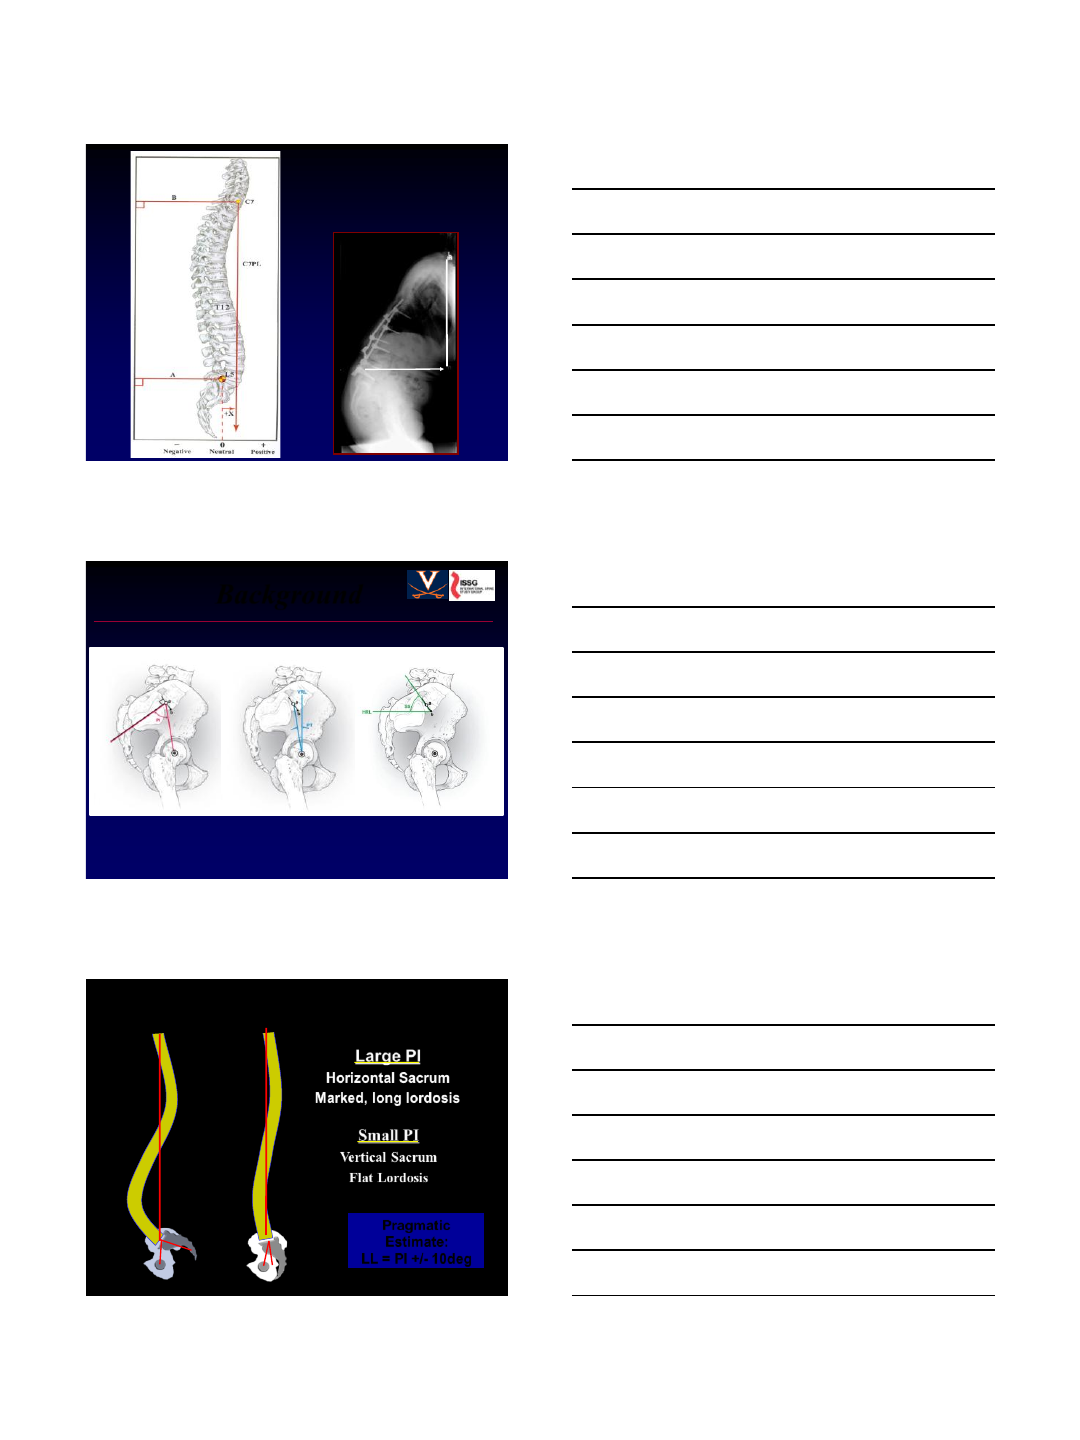

Small PI

Vertical Sacrum

Flat Lordosis

Large PI

Horizontal Sacrum

Marked, long lordosis

Pelvic Incidence and Lordosis

Pragmatic

Estimate:

LL = PI +/- 10deg